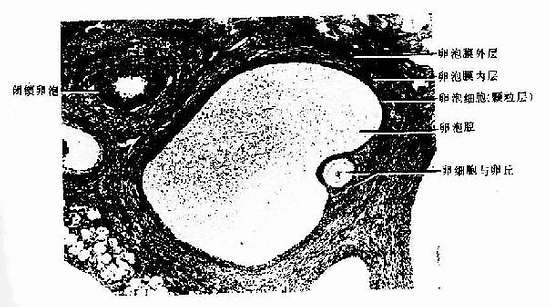

4.成熟卵泡 成熟卵泡(mature follicle)是卵泡发育的最后阶段。卵泡体积很大,直径可达20mm,并向卵巢表面突出(图17-1,17-5)。成熟卵泡的卵泡腔很大,颗粒层甚薄,颗粒细胞也不再增殖。此时的初级卵母细胞又恢复成熟分裂,在排卵前36~48小时完成第一次成熟分裂。产生1个次级卵母细胞(secondary oocyte)和1个很小的第一极体(first polar body)。第一极体位于次级卵母细胞和透明带之间的卵周间隙(perivitelline space)内。次级卵母细胞随即进入第二次成熟分裂,停止于分裂中期。人每个月经周期,可有若干个原始卵泡生长发育,通常只有1个卵泡发育成熟并排卵。

图17-5 猫卵巢内的近成熟卵泡 HE×160